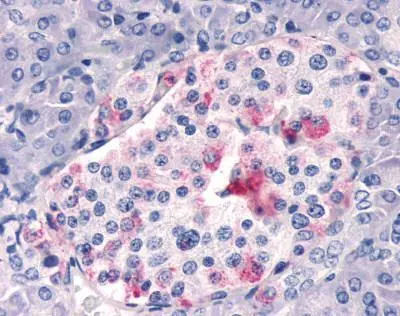

Anti-Respiratory Syncytial virus A2 G protein antibody used in Immunohistochemistry (IHC). GTX70381

GTX70381 IHC Image